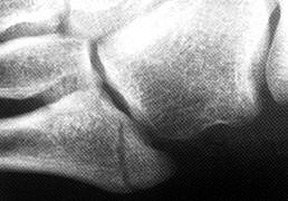

The development of a secondary center of ossification at the proximal end of the fifth metatarsal appears in girls ages 9 to 11 and boys ages 11 to 14, appearing as a fleck of calcification adjacent to the fifth metatarsal shaft on plain films. The apophysis has an oblique orientation, with the radiolucency aligned parallel to the fifth metatarsal diaphysis. (Figure 4) The orientation of the radiolucency is crucial to differentiating this normal finding from an acute fracture.

Fig. 4: Apophysis of the fifth metatarsal.